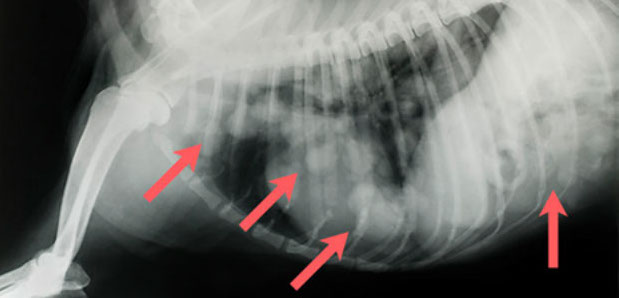

Mehrfachfrakturen nach Autounfall mit Lähmung der Hinterextremitäten, Hund